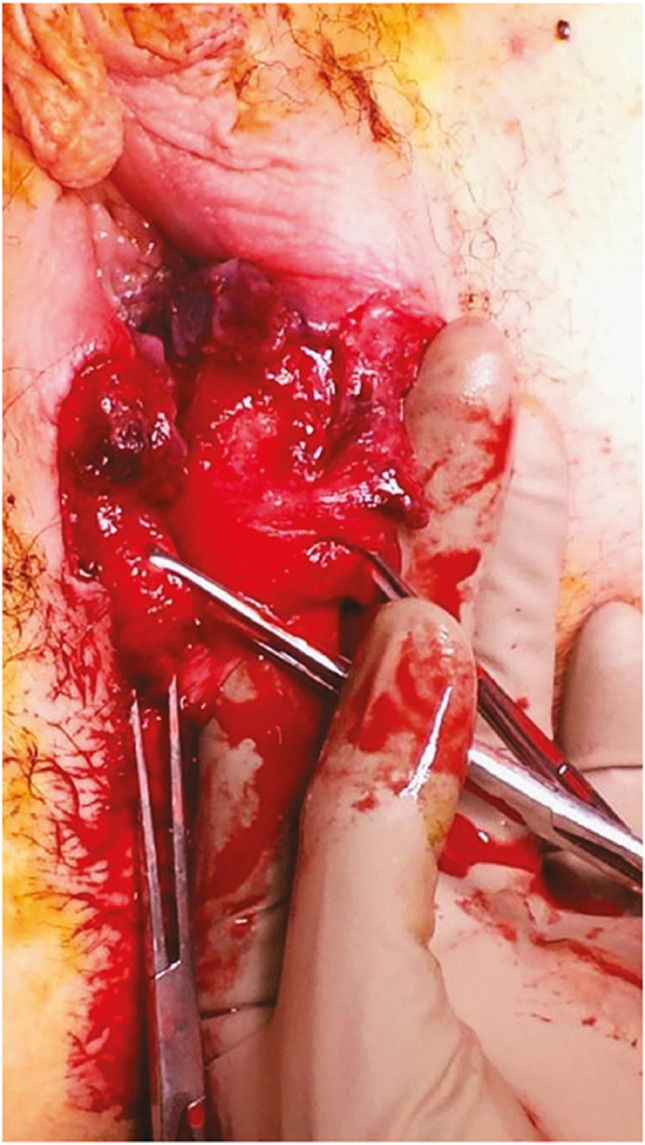

Observation of a defect between the lower urinary tract structure (urethra, bladder) and vagina (vesicovaginal fistula, Fig. 1) and/or uterus (and/or cervix) that may occur across a spectrum of tissue loss (Fig. 2), with variable appearance and with or without observation of a.

Fig. 1.

Obstetric vesico-vaginal fistula during repair [37].

Source: Reprinted by permission from Springer Nature